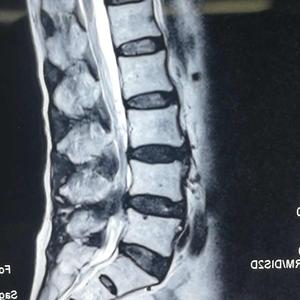

疾病介绍 概念 胫腓骨干骨折(fractures of the shaft of the tibia and fibula)指发生于胫骨平台以下至踝部部分的骨折,为长骨骨折中最为多见的一种,约占全身骨折的13%17%,以青壮年和儿童居多。 病因 如:压砸、冲撞、打击致伤 如:高处跌下,跑跳的扭伤或滑倒 直接暴力 间接暴力 临床表现及检查 临床表现: 伤侧小腿疼痛、肿胀、压痛、功能障碍,局部有畸形、反常胫腓骨骨折护理 专科护士小组 查 房 内 容 查 房 目 标 了解胫腓骨骨折发病机制 熟悉胫腓骨骨折临床表现 掌握胫腓骨骨折围手术期护理 掌握胫腓骨骨折术后功能锻炼 病 例 介 绍 患者男性,40岁,因车祸致左小左足首腓骨骨折~通院終了まで テーマ: 骨折治療内容 治療費 骨折治療をまとめた記録です。 左足首腓骨骨折と一言で言っても、症状や医師の治療方針によって治療内容や支払い費用が変わると思いますので、あくまで当方の場合は

左侧胫腓骨粉碎性骨折都是因为胫腓骨受到直接的暴力而导致,例如车祸撞击伤或者被重物压砸伤、打击伤而引起。 如果是闭合性骨折可以给予手术切开复位,利用钢板或者交锁髓内钉来做内固定手术。 如果骨碎块粉碎比较严重,利用髓内钉或者钢板固定后,必须要适当地利用钢丝来环扎局部骨碎块的情况,从而避免移位。 如果是开放性的骨折,周围的软组织 你好,左小腿胫腓骨中下段骨折,使用髓内钉和钢板手术固定,是否能评上伤残。 没有符合您的答案? 立即在线问律师 如果是工伤的话,构成十级伤残,如果是交通事故或者其他原因导致损害的,要以具体的伤残鉴定结果为准。 法律意见 需要根据伤情鉴定以及之后花费的费用确定。 法律依据 侵权责任法 第十六条 人身损害赔偿侵害他人造成人身腓骨(ひこつ、ラテン語 fibula、英語 calf bone)は、四肢動物の後肢を構成する骨である。脛骨とともに膝から足首までを構成し、脛骨に対して外側背面を通っている。 脚および足の腓骨側を腓側(ひそく)という。医学用語の外側(がいそく)および日常語の外側(そとがわ)と同じである。腓側の反対側を脛側(けいそく)と呼ぶ。

首页 > 外科 > 骨科 > 开放性骨折 左小腿胫腓骨开放性骨折,内固定术后70天 发病时间:不清楚 病情描述: 14年10月发生车祸,左小腿胫腓骨开放性骨折。 内固定手术后两个月拍片,骨折线明显,未见骨伽,医生很惊讶,说愈合的太慢了。 但我自己觉得能弃拐下地走路,走两百米左右,腿会有点疼,需要休息。 请问,这样我大概多久才能正常走路? 可不可以慢慢走